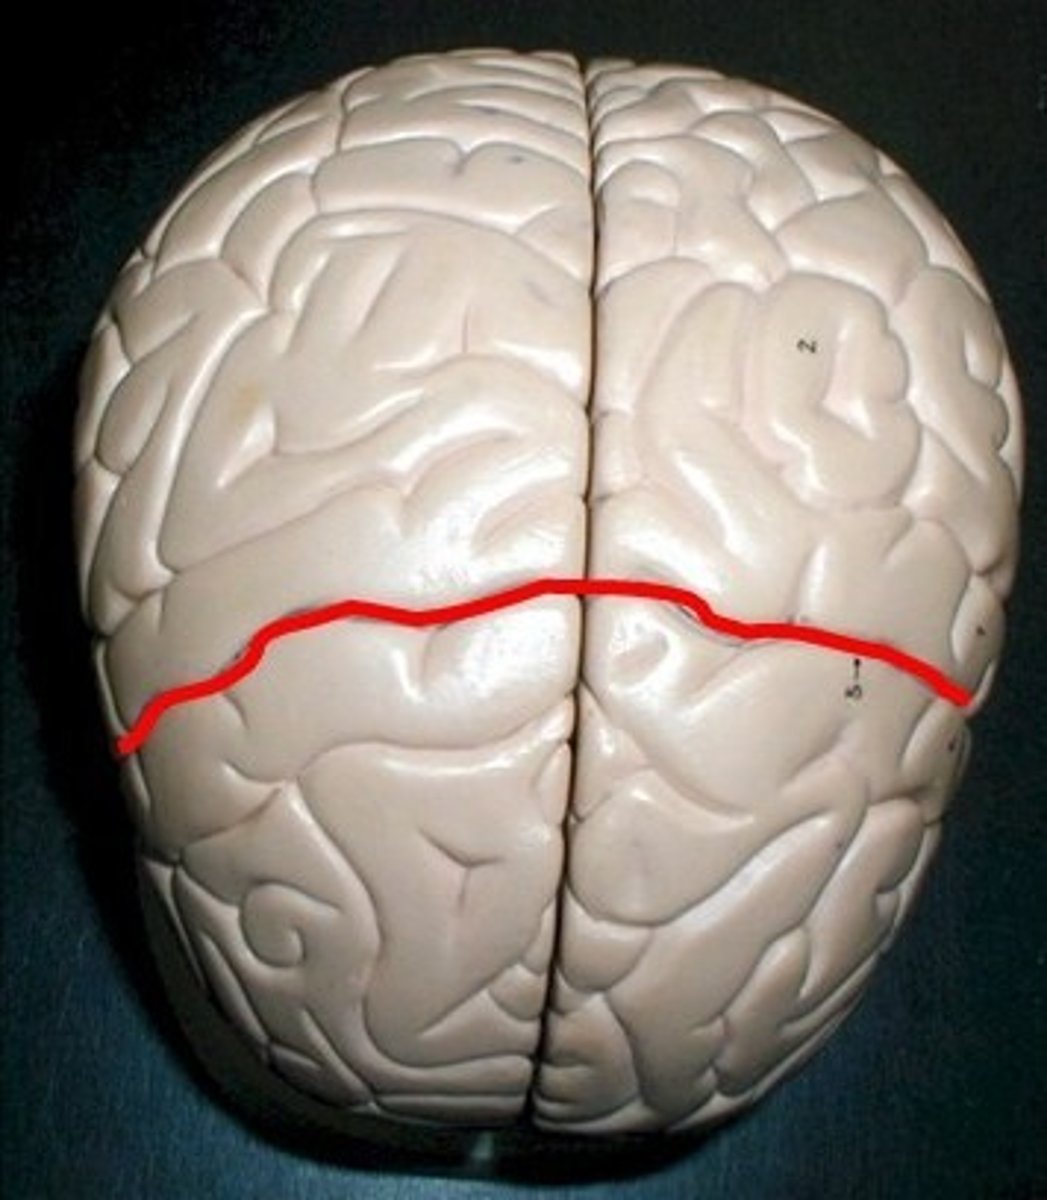

longitudinal fissure

central sulci